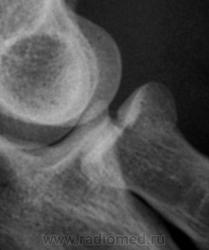

Фрагменты с увеличением.